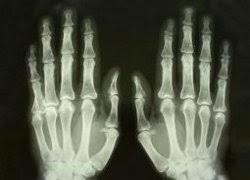

RAIO X

RADIOGRAFIA

Radiotransparente: estrutura deixa passar⇒preto (ex:pulmão)

Radiopaco: estrutura absorve⇒branco (ex:osso)

Quais as diferentes densidades?

AR(MAIS RADIOTRANSPARENTE)

GORDURA

PARTES MOLES

OSSO(MAIS RADIOPACO)